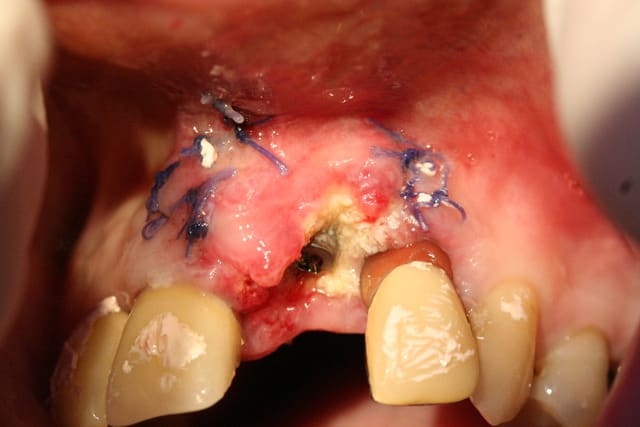

Le cas EII sur 12

positionnement de l'implant en ménageant un espace en vestibulaire qui st comblé avec de l'os synthétique car l'espace est important et il y a une perforation de la corticale vestibulaire en regard de l'apex de la dent.

pour recouvrir tout cela et gagner un peu de volume vestibulaire

un lambeau palatin pédiculé qui après une rotation va recouvrir l'implant et la greffe.

j'ai désépithélialisé la portion que j'ai glissé sous le lambeau vestibulaire, par contre j'ai laissé l'épithélium sur la partie qui recouvre l'implant et qui est "à l'air libre"